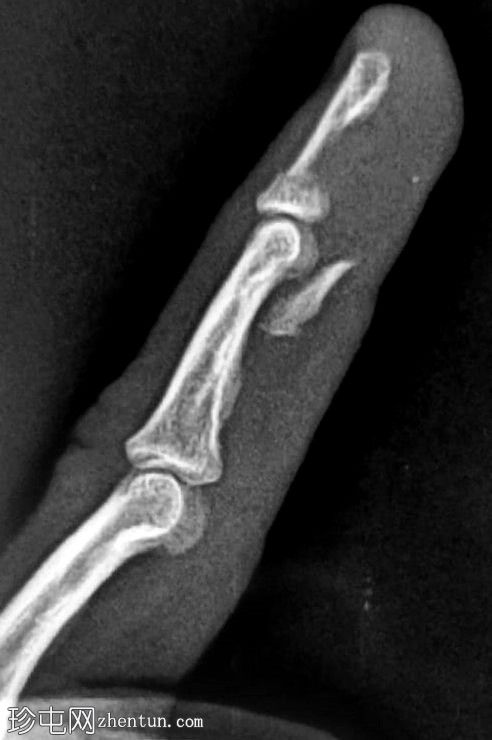

完整的屈指浅肌腱滑脱。连续短轴图像显示屈指浅肌腱向外侧延伸至深屈指肌。指深肌腱完好,附着于远端指骨撕脱的骨碎片(11 x 4 毫米)。它位于中节指骨远端骨干和指头水平。远端指骨掌侧短轴和长轴方向存在缺损。无腱鞘炎/关节积液。